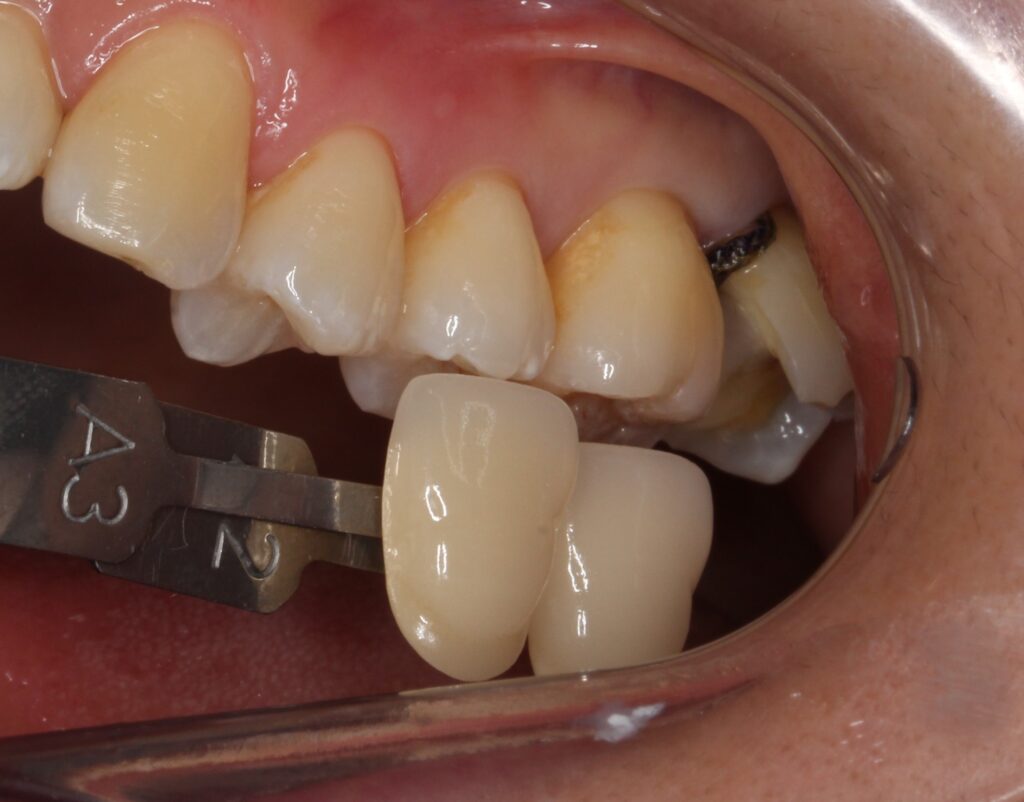

症状が落ち着いたのを確認した後に、形を整えて、型取りを行います。

セラミックインレーにて修復を行います。その歯にぴったりと合うように専門の歯科技工士がセラミックを製作します。

セラミックがセットされました。

綺麗に仕上がりましたね(^^)/

隙間が無く、今後も虫歯が入り込むリスクが無くなりますね。